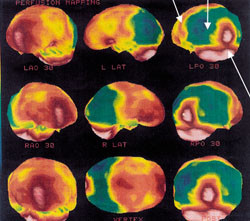

Ved Alzheimers sykdom ansees redusert perfusjon avgrenset til hjernens temporo-parietale regioner for å være en markør for Alzheimers sykdom og kan være uttrykk for substanssvinn i disse områdene (fig 3). I en nylig publisert studie, hvor man korrelerte cerebrale SPECT-forandringer hos pasienter med Alzheimers sykdom med senere autopsifunn, konkluderes det med at SPECT-undersøkelse er et nyttig hjelpemiddel ved klinisk mistanke om Alzheimers sykdom (23). Imidlertid setter andre forfattere spørsmålstegn ved SPECT-metodens presisjon og gyldighet i diagnostikken ved denne problemstillingen (24). Gjentatte undersøkelser over tid ved usikre kliniske symptomer kan gi diagnostisk tilleggsinformasjon, men også her mangler forskningsdokumentasjon. Metoden anbefales imidlertid brukt på spesialistnivå som et supplement til cerebral CT eller MR ved mistanke om patologiske forhold frontalt (25). SPECT-metoden ser ut til å være spesielt velegnet for å påvise patologi i frontallappene i tidlig fase (26) (fig 4). Hypometabolisme begrenset til subkortikale strukturer, som man kan se ved subkortikal demens, kan imidlertid være vanskelig å påvise ved denne metoden. Ifølge den amerikanske konsensusrapporten (18) gir ikke SPECT-undersøkelser tilleggsinformasjon av betydning i forhold til dagens kliniske diagnostiske kriterier for demens, og metoden anbefales derfor ikke brukt rutinemessig.